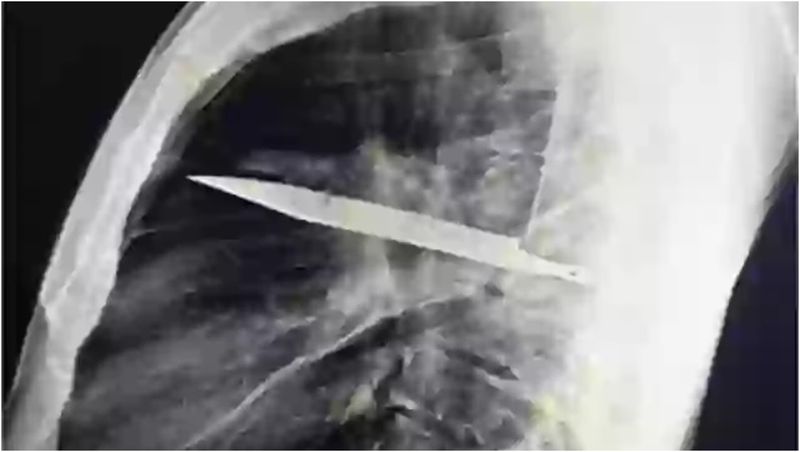

Radiografia a dezvăluit că bărbatul avea un cuțit de dimensiuni considerabile înfipt adânc în piept!

După ce au solicitat o radiografie, a fost găsit un „obiect metalic” imersat, iar medicii și-au dat seama că este o lamă lungă de cuțit, înconjurată de „puroi și țesut necrotic”.

În urma discuțiilor cu pacientul, s-a aflat că acesta fusese înjunghiat în urmă cu 8 ani, iar lama metalică intrase în corp prin umărul drept.